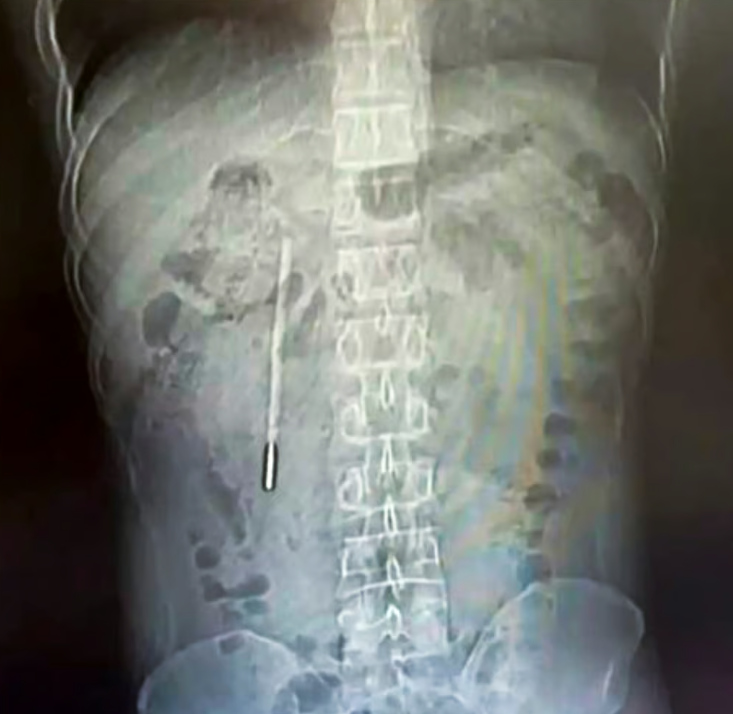

Инородный предмет был обнаружен в двенадцатиперстной кишке. Кончик термометра упирался прямо в стенку кишечника и создавал риск перфорации и сильного внутреннего кровотечения. Тогда Ван и рассказал врачам, что проглотил ртутный градусник, когда ему было 12 лет. Поскольку серьёзных симптомов и неудобств тогда это не вызывало, про градусник он со временем просто забыл.

Хирургам потребовалось 20 минут, чтобы извлечь инородное тело.

«Операция была очень сложной, поскольку термометр находился в организме пациента в течение длительного времени и располагался близко к желчным протокам, что создавало значительный риск повреждения стенки кишечника», — пишет издание.